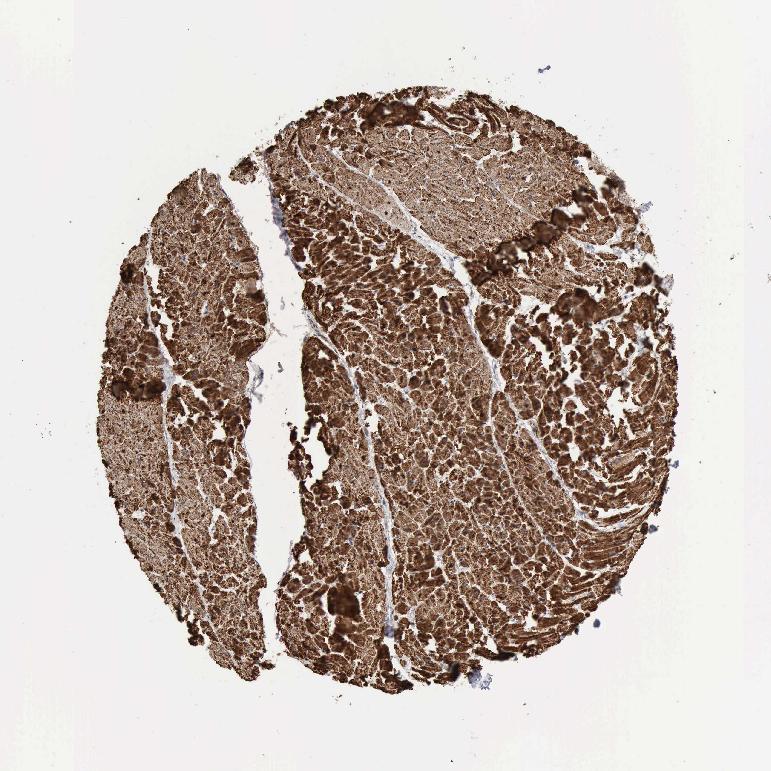

HEART MUSCLE - Antibody stainingi

Antibody staining in the annotated cell types in the current human tissue is reported as not detected, low, medium, or high, based on conventional immunohistochemistry profiling in selected tissues. This score is based on the combination of the staining intensity and fraction of stained cells.

Each image is clickable and will lead to virtual microscopy that enables deeper exploration of all samples and also displays staining intensity scores, fraction scores and subcellular localization as well as patient and tissue information for each sample.

Antibody HPA001097

Cardiomyocytes High